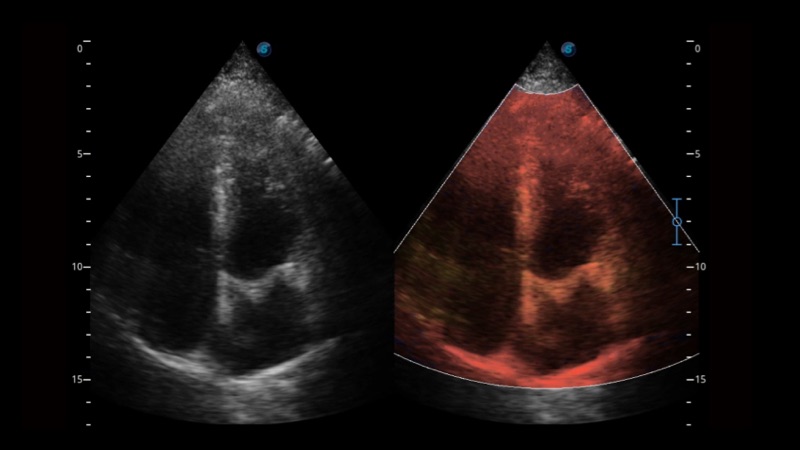

凭借狗万官方网站先进的成像技术和优异的探头技术提供的清晰的图像表现,您可以更自信地做出临床决策。